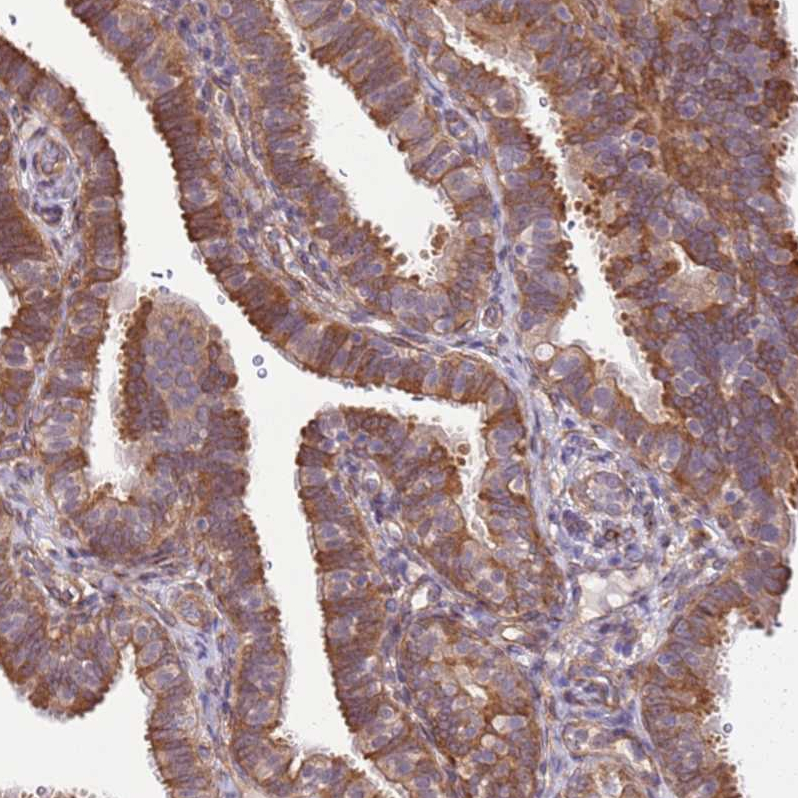

Immunohistochemical staining of human fallopian tube shows strong cytoplasm granular positivity.